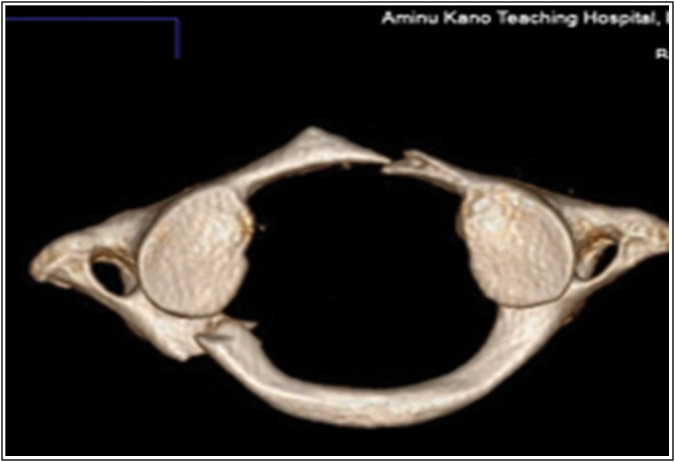

Results: There were 143 patients with head injuries studied; 90.2% of them were males. The mean age of the patients was 28.87 ± 15.93 years. The most common cause of injury was road traffic accidents in 110 (76.90%). The prevalence of CSI was 11.2%. Majority of the patients with CSI in this study (56.25%) had a mild head injury, 25% had a moderate head injury, and 18.75% had a severe head injury. The lower cervical spine was the most frequently injured segment in this study, involving 10 patients. Multi-level cervical vertebral body fractures of C3 to C6 were the most common form of CSI in this segment.

Abstract Image